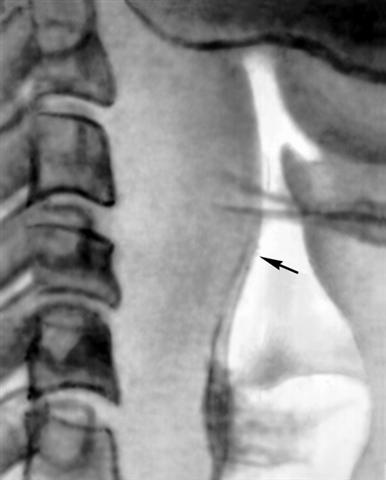

Рис. 3. Рентгенограмма шеи при заглоточном абцессе (боковая проекция): стрелкой указан резко выбухающий кпереди контур тени заглоточного пространства.